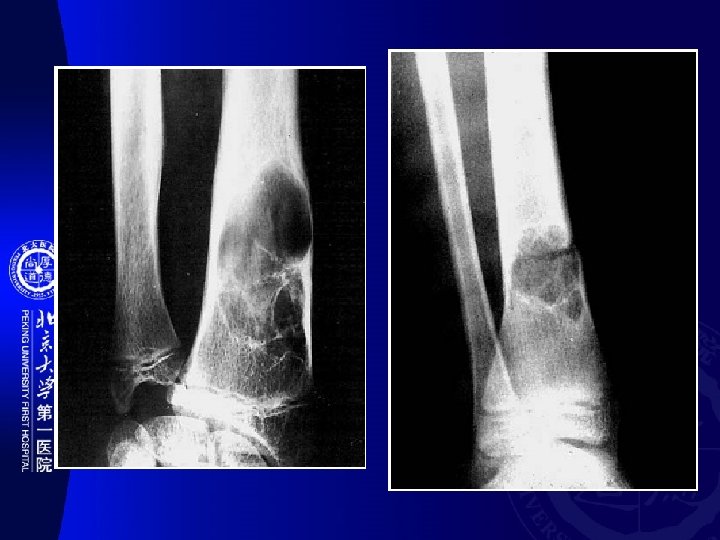

骨干 Diaphysis 干骺端 Metaphysis 骨骺 Epiphysis Other Myeloid 多发性骨髓瘤(Multiple myeloma) Epithelial 釉质细胞瘤(Adamantinoma) PNET 尤文氏瘤 (Ewing’s sarcoma) Osteoblast 骨样骨瘤 成骨细胞瘤(Osteoblastoma) 骨瘤 (Osteoma) 骨肉瘤(Osteosarcoma) Chondroblast 软骨瘤 软骨肉瘤(Chondrosarcoma) 骨软 骨瘤 软骨粘液样纤维瘤 Fibrous 非骨化性纤维瘤(nonossifying fibroma) 纤 维肉瘤(Fibrosarcoma) Chondroblast 成软骨细胞瘤(Chondroblastoma) Myeloid 骨巨细胞瘤(Giant cell tumor of bone) Notochord 脊索瘤(Chordoma)

� 骨好� 部位(SITE OF LONG BONE INVOLVEMENT ) (most primary bone tumors have favored sites within long bones; this may provide a clue to diagnosis). Diaphyseal intramedullary lesions: Diaphyseal lesions centered in the cortex: 釉� 瘤, 骨� 骨瘤 尤文氏瘤,淋巴瘤, 骨髓瘤,� �� 构不良,内生� 骨瘤 Metaphyseal intramedullary lesions: 骨肉瘤、� 骨肉瘤、 �� 肉瘤、�� 性骨囊� 、 � 脉瘤� 骨囊� Metaphyseal lesions centered in the cortex: 非骨化性�� 瘤(NOF) Epiphyseal lesions: � 骨母� 胞瘤 (Ch) and 骨巨 � 胞瘤(GCT) Metaphyseal exostosis: 骨� 骨瘤